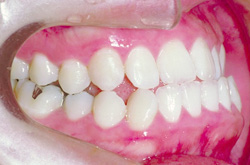

側 面

before

after